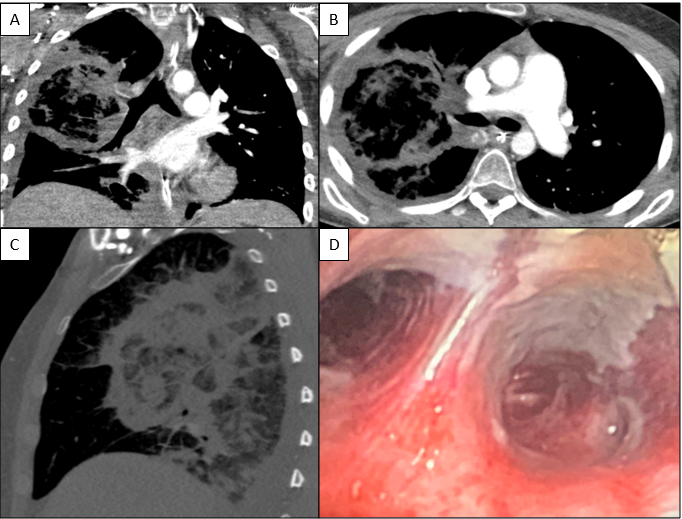

A 41-year-old male was admitted with myasthenia gravis exacerbation and respiratory difficulty. He was diagnosed with myasthenia gravis in 2004, underwent a thymectomy in 2010, and was taking prednisone (20 mg daily). He presented to another hospital one month ago with fever, chest pain, and shortness of breath. He was treated with antibiotics and antifungals for pneumonia, along with 5 days of immunoglobulin for a possible myasthenia gravis crisis, but showed no improvement. After admission, a CT scan revealed diffuse bilateral mixed airspace and ground-glass opacities without pleural effusions, most concerning for multifocal pneumonia. A bronchoalveolar lavage (BAL) with Gomori methenamine silver (GMS) staining showed hyphal and yeast elements. Both BAL and urine Histoplasma antigen tests were positive. He was started on posaconazole (300 mg daily), which led to an improvement in symptoms, and he was subsequently discharged. After 6 weeks of culture, macroscopic and microscopic features of the colony confirms Histoplasma capsulatum (Figure 1).

Diagnosing histoplasmosis involves clinical suspicion, radiological studies, and laboratory tests. The most common radiographic findings are diffuse reticulonodular pulmonary infiltrates. Cavitations are seen in chronic cavitary pulmonary histoplasmosis, and mediastinal or hilar lymphadenopathy is often present. In immunocompetent individuals, infections may lead to development of granulomas that may or may not be necrotizing.

Culturing Histoplasma from clinical specimens is definitive, but it can take 4-8 weeks due to the slow growth of the fungus. The colonies appear white at young growth, have a cottony, cobweblike-aerial mycelium and can mature into brown or grey color on reverse (Figure 1, top) 8. Microscopic examination of mold colony using lactophenol cotton blue preparations reveals the characteristic large, rounded, tuberculate macroconidia (circular structures with roughened/spiked edges) originating from short, hyaline conidiophores (Figure 1, bottom). Histoplasma capsulatum appears as small (2-5 μm), oval, intracellular yeast cells typically found within macrophages. The yeast may exhibit a clear space which may appear like a capsule, but is actually a retraction artifact due to the processing of the specimen. Staining with GMS or periodic acid-Schiff (PAS) highlights the yeasts9. Molecular methods such as PCR and sequencing have been shown to detect cases of Histoplasma as well.